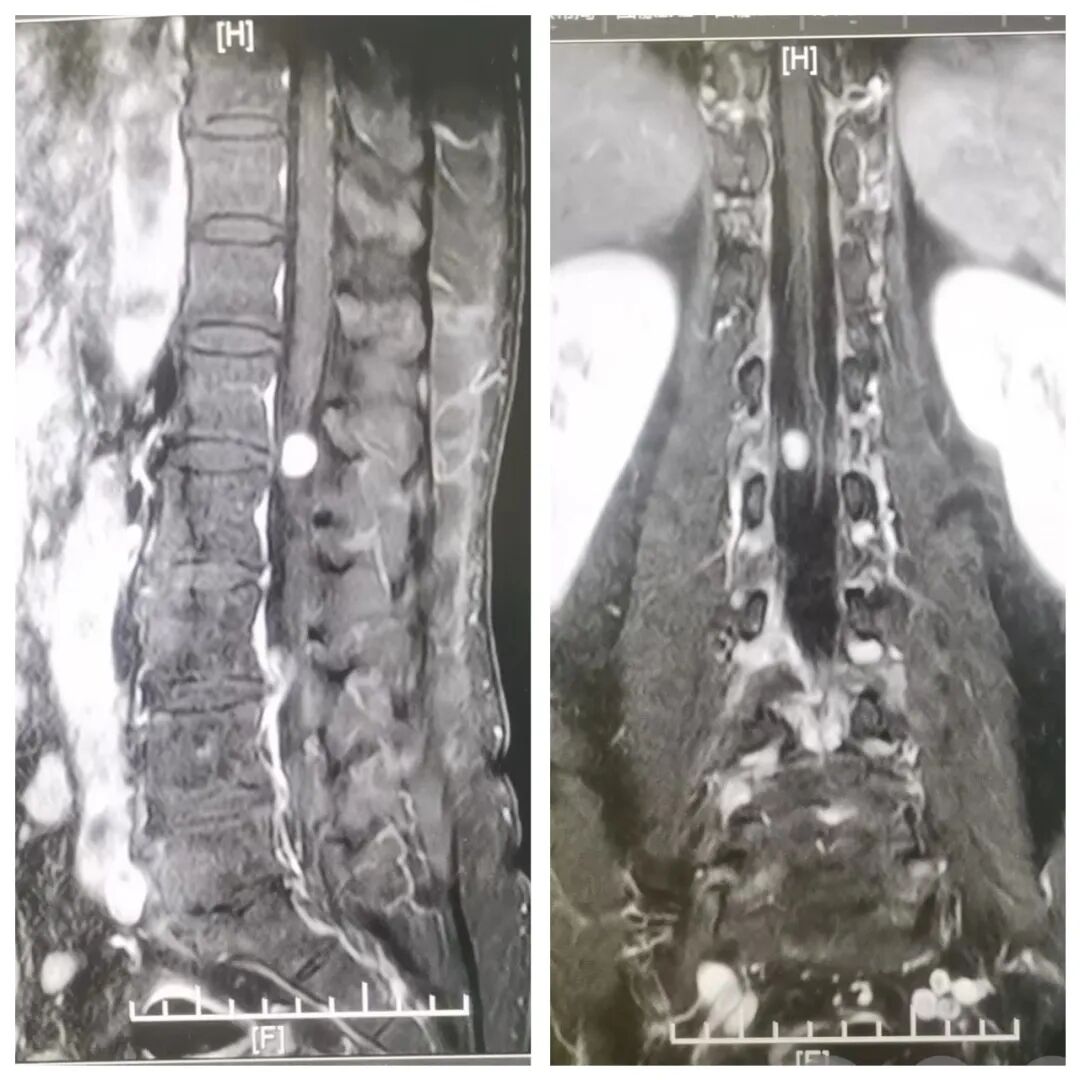

通过腰椎MRI检查提示:腰1-2椎间隙层面椎管内占位,考虑椎管内神经纤维瘤可能。

无疑,椎管里这个”小灯泡“的占位就是造成周先生腰腿疼痛、无法行走的“元凶”,随着身体的走动还会闪着疼。

是目前明确诊断椎管内肿瘤最重要、最有价值的手段。根据临床表现要选择合适部位的磁共振检查,如颈椎、胸椎、腰骶椎等,有时候需要多个部位同时检查以明确诊断。部位选择不当可能造成误诊漏诊。MRI能直接观察肿瘤形态、部位、大小、数目及与脊髓的关系,还能显示肿瘤囊变、出血、脊髓空洞和脊髓水肿,对于制定治疗方案和手术计划具有重要的指导意义。